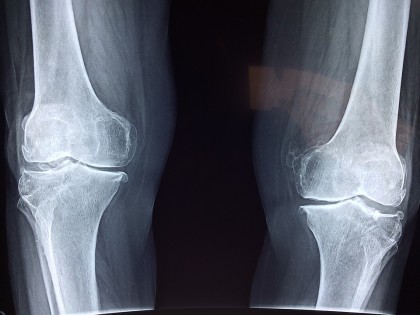

Osteoartrita este cauzată de distrugerea cartilajului - țesutul care protejează articulația și permite mișcarea lină. Greutatea corporală în exces pune o presiune ridicată pe aceste articulații și duce la lezarea cartilajului. În plus, un volum mare de grăsime poate duce la dezvoltarea substanțelor din sânge care produc inflamație - un alt factor de risc pentru osteoartrită.

Autorii studiului de față au investigat efectul pierderii în greutate asupra degenerării structurilor genunchiului: menisc, cartilaj articular, măduva osoasă. Pentru aceasta, au folosit imaginile RMN.

Rezultatele au arătat că pacienții cu 5% scădere în greutate au avut o degenerare a cartilajului mai lentă decât cei care și-au menținut greutatea. La persoanele cu 10% scădere în greutate încetinirea degenerării a fost chiar mai accentuată. Pe lângă efectul asupra cartilajului, autorii studiului au mai observat o degenerare mai lentă a meniscului. Studiul a fost publicat în revista Radiology.